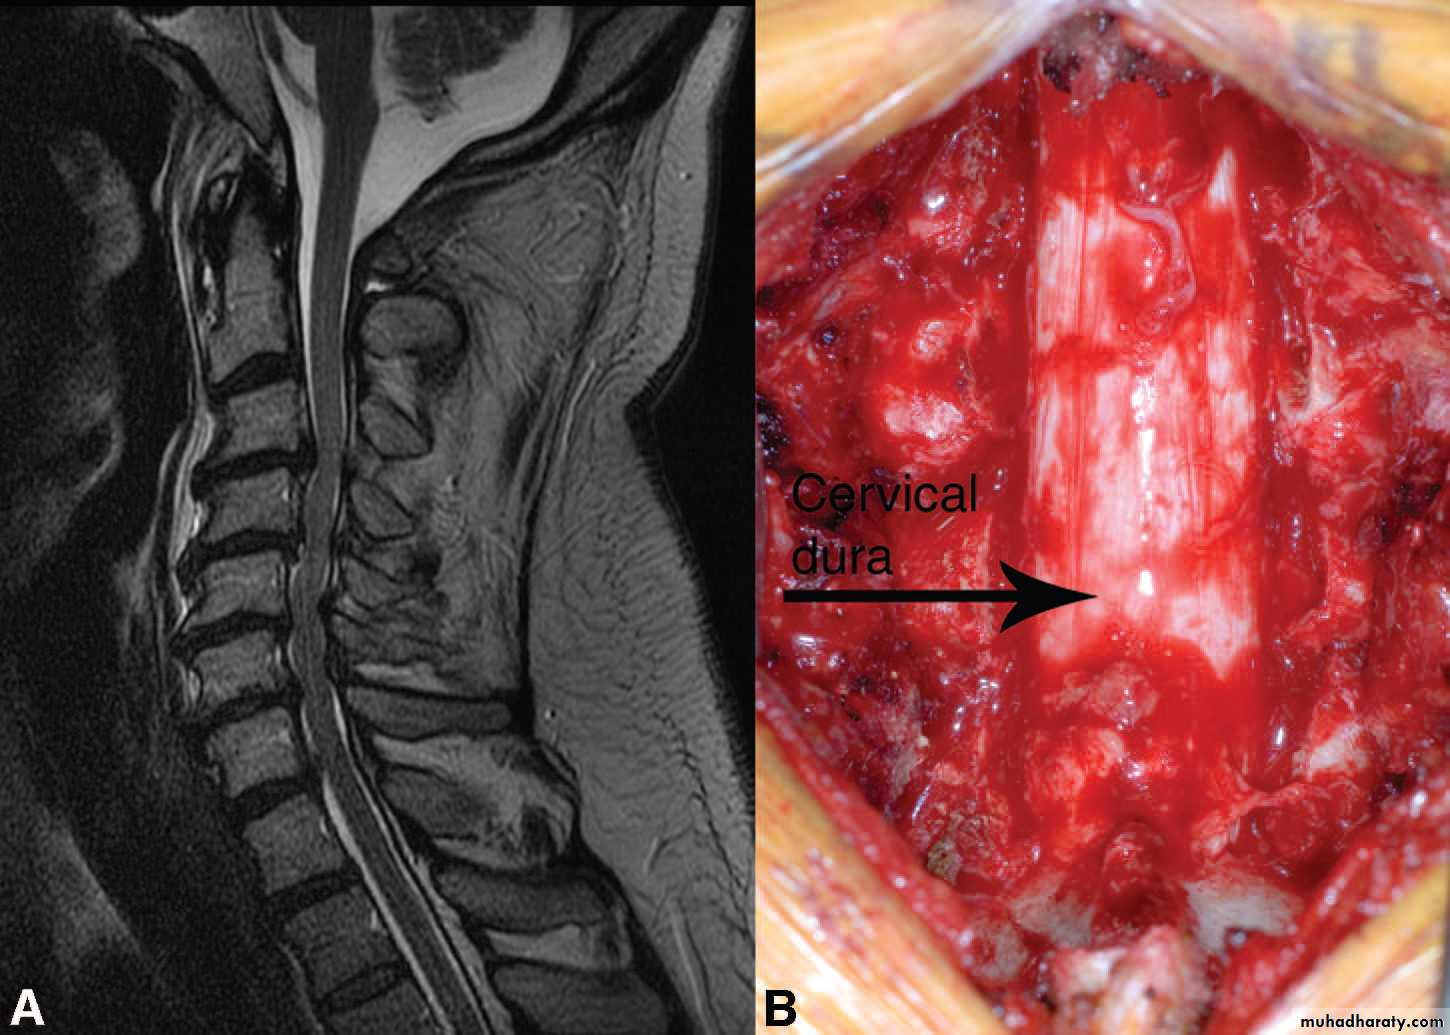

Cervical disc herniation

The clinical presentation:1-patient is usually young age develop pain in the cervical area that may radiate to the arm .

2-if the herniation is lateral so lead to radicular symptoms.

3- But if the herniatin is central so lead to compression on the spinal cord itself causing spastic quadriplegia with sensory level and incontinence.

The investigation:

1- MRI of spine :to see the direction and extent of the compression .Treatment :